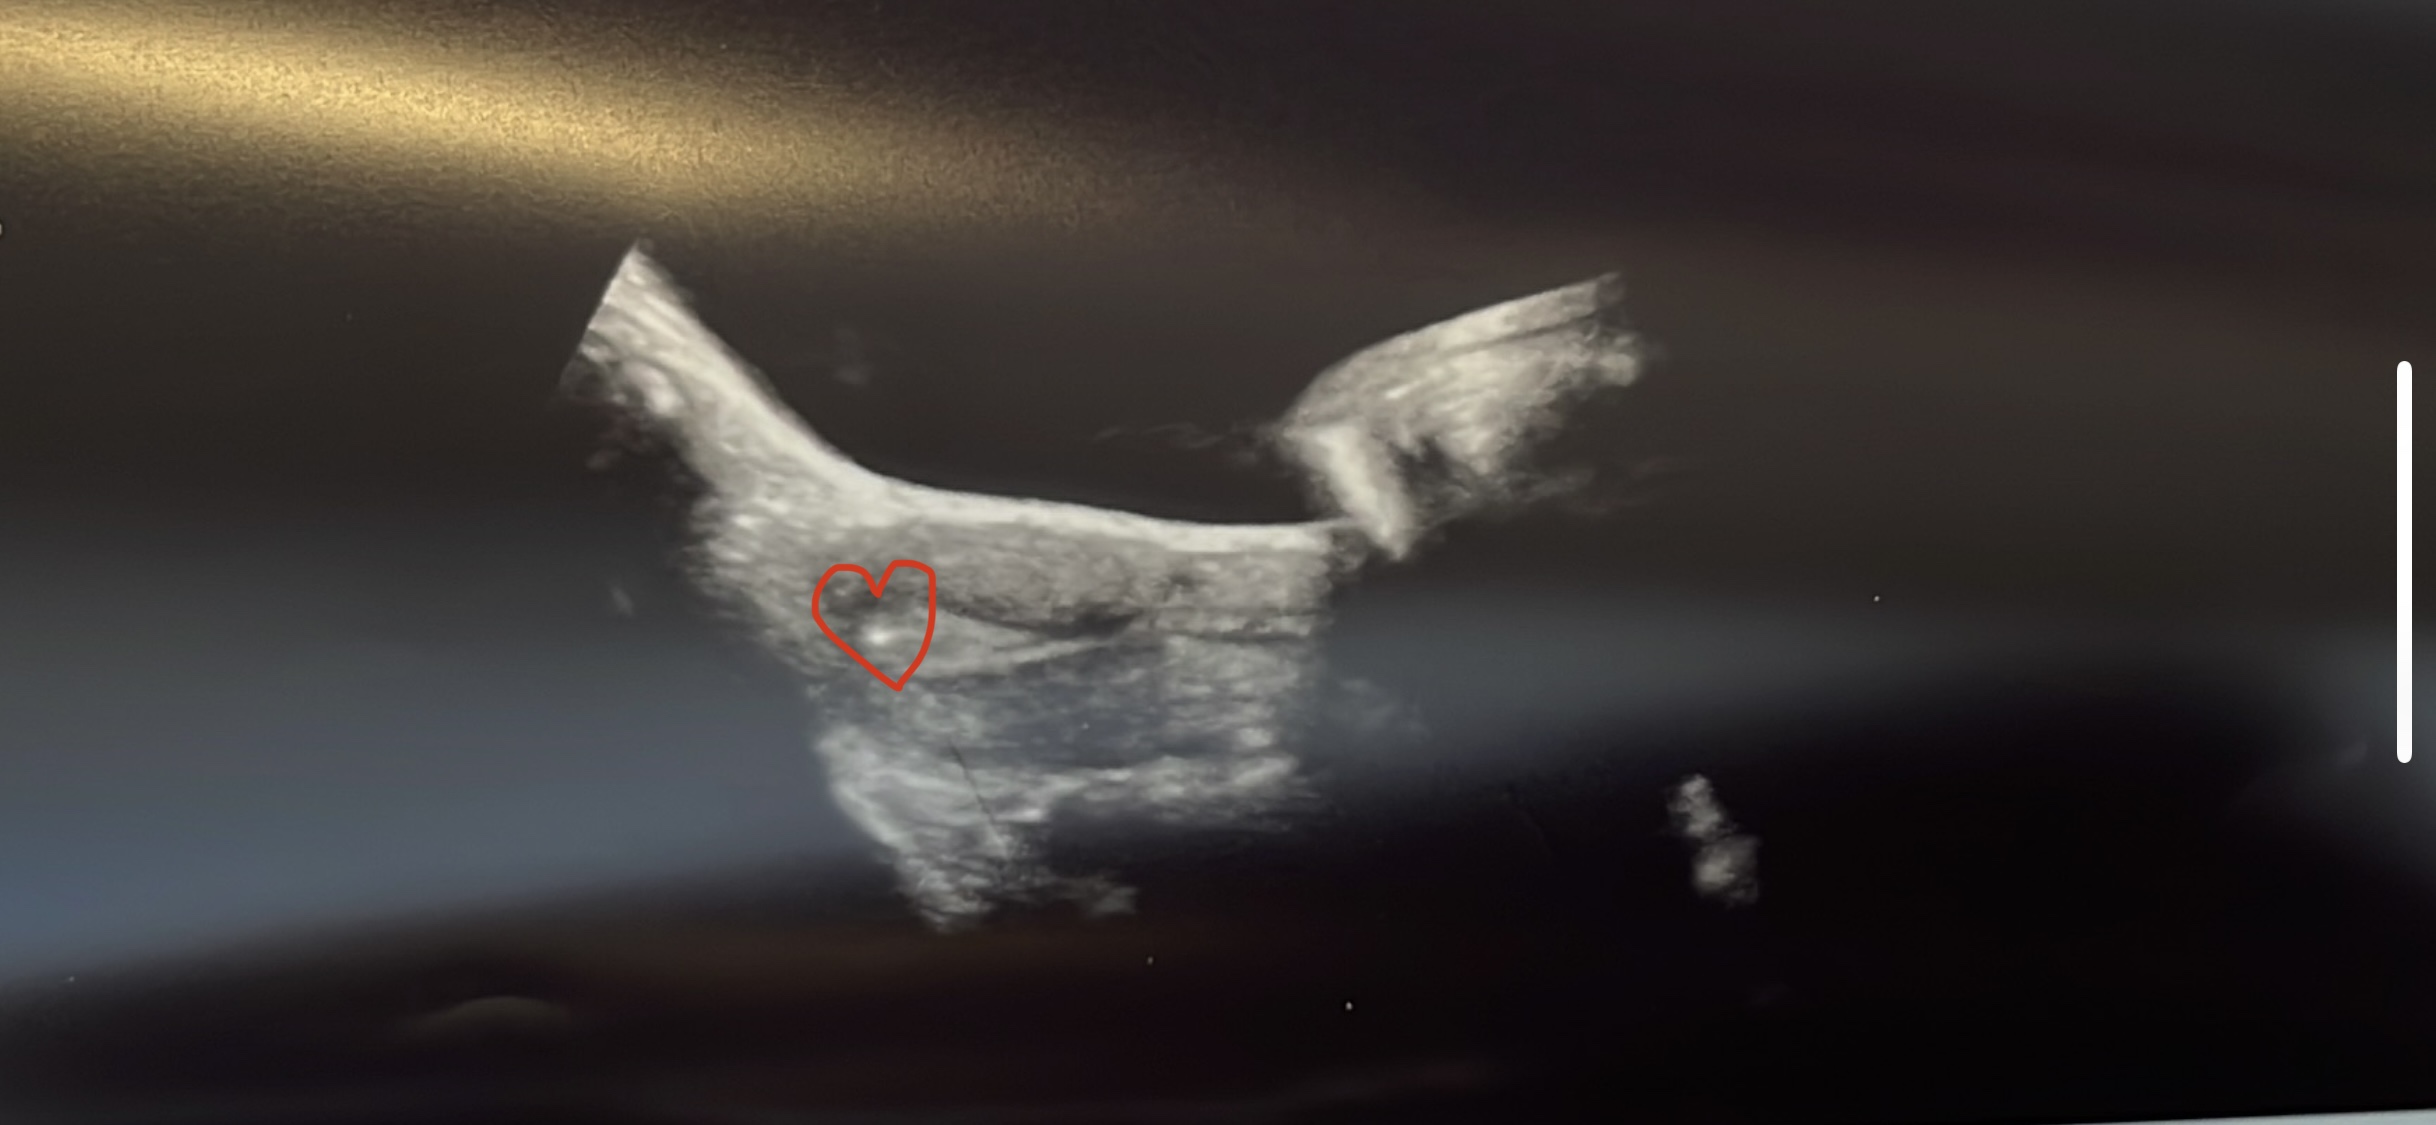

Um 14:14 durfte eine wunderschöne geschlüpfte blastozyste bei mir einziehen ❤️ alles hat super geklappt. Ich bin gespannt wie der bluttest am 24.11 ausgeht.